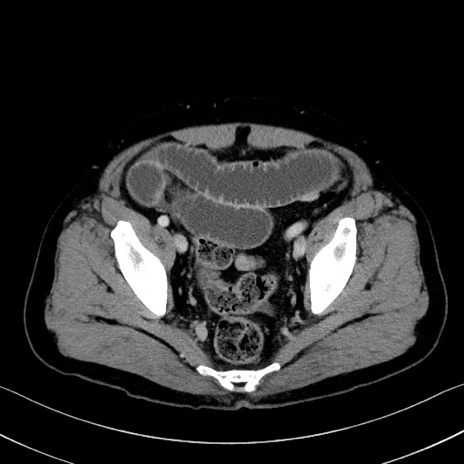

症例35(横断像)

【症例】70歳代 男性

【主訴】腹部膨満、嘔吐

【現病歴】昨日より腹部膨満感出現。本日増悪し、仙痛出現。嘔吐あり、受診。

【既往歴】糖尿病、胆摘後

【身体所見】BP 149/80mmHg、HR 74/min、BT 35.9℃、腹部:膨満、軟、圧痛なし。腸雑音減弱あり。上腹部正中切開瘢痕あり。

【データ】WBC 13500、CRP 1.72